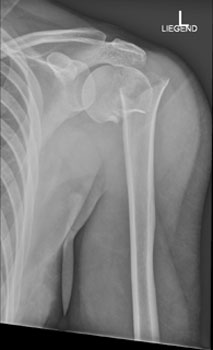

Die Röntgenaufnahme der Schulter in zwei Ebenen ist die Untersuchung der Wahl zur Beurteilung der Knochenstrukturen und der Gelenkstellung.

Hier sehen Sie die Aufnahmen im vorliegenden Fall:

Schulter nach Neer